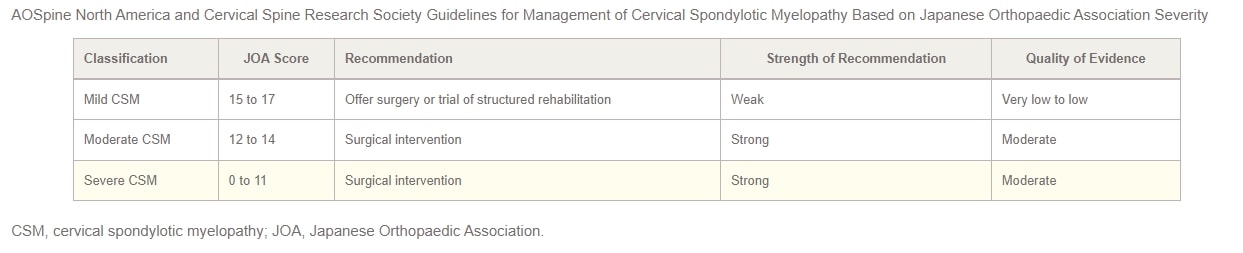

I 2017 blev AOSpine North America og Cervical Spine Research Society (CSRS)) har i fællesskab udgivet retningslinjer for behandling af CSM baseret på sværhedsgraden. For patienter med mild CSM bør mulighederne for kirurgisk indgreb eller et overvåget forsøg med struktureret genoptræning præsenteres. Hvis ikke-operativ behandling ikke giver bedring, eller hvis patientens tilstand forværres, anbefales kirurgisk indgreb. I tilfælde af moderat til svær CSM anbefaler retningslinjerne kraftigt et kirurgisk indgreb. Patienter med cervikal kompression, men uden klare tegn på myelopati eller rodkompression, bør modtage rådgivning om risikoen for sygdomsprogression, undervisning i symptomer, man skal være opmærksom på, og regelmæssig klinisk opfølgning.

Endelig foreslår forfatterne, at man overvejer enten kirurgisk behandling eller struktureret genoptræning med tæt opfølgning for patienter, der udviser kompression af livmoderhalsen sammen med tegn på radikulopati. Retningslinjerne for behandling af CSM i 2017, stratificeret efter sværhedsgrad, er opsummeret i tabellen nedenfor: